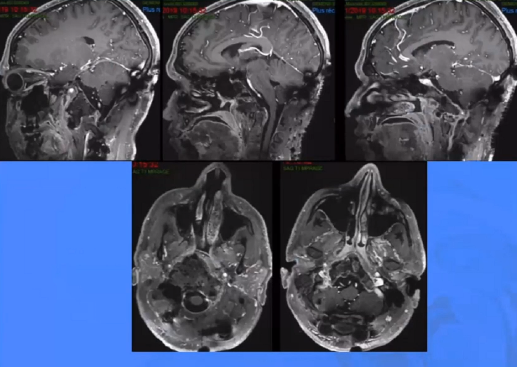

▼这个病例,它影响了颈1颈2,然后没有侵袭到硬膜内,我就不考虑用内镜了。考虑到脑脊液的释放等问题,这里我用了后外侧的一个入路。利用45度的内镜往上看,往上磨除岩骨的后方,可以一直暴露颈内动脉的岩骨段,然后海绵窦段。然后在显微镜下我们可以进行双手的操作,神经外科医生就比较熟悉的了。我们在做手术切除肿瘤切完了之后,还要进行固定。

▼这是一个较大肿瘤的案例,它严重影响到枕髁,我们用神经内镜,通过抽吸可以切除大部分,然后和显微镜配合。

▼这是术后的MRI